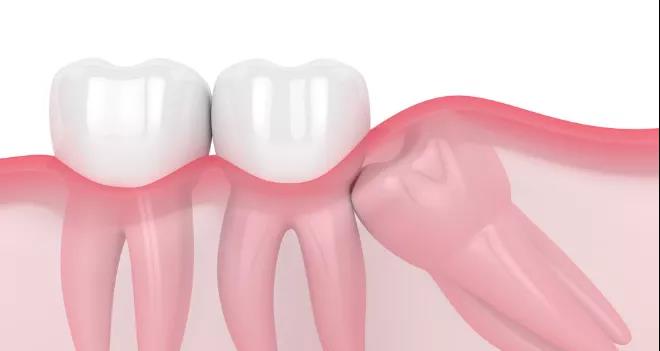

如果智齿的萌生空间不足,与邻牙无法形成良好的邻接关系,就容易造成塞牙,导致邻牙龋坏或者牙槽骨吸收。

并且智齿生长的角度往往是歪七扭八的,可能会顶着相邻牙齿的齿面,让被挤压的牙齿有被蛀的风险。

智齿阻生的部分情况

最让人头疼的是横着长的智齿,没有萌出反而顶着邻牙的牙根,导致牙根之间的牙槽骨被吸收。

而且牙槽骨吸收所造成的的伤害是是无法挽回的,最终发展下去,会两败俱伤。

不仅智齿需要拔除,邻牙可能得一块儿被拔掉,十分影响咀嚼功能。